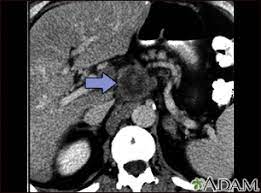

Abdominal Ct Scan Information Mount Sinai New York from ssl.adam.com Right now, ct scans are not used routinely to evaluate the breast. Computed tomography (ct or cat) scan. Can a ct scan detect ovarian cancer? Each has its own strengths. There is wash out of contrast in all abdominal structures except for fibrotic tissue, because fibrotic tissue has a poor late wash out and will become relatively dense good quality ct scanning is the most important factor for the diagnosis of pulmonary emboli. A ct scan is one of the most frequently utilized exams to detect cancer and to show things such as a tumor's shape and size. Radiologist— a medical doctor specially trained in. This advanced nuclear imaging technique combines positron emission tomography (pet) bone scan:

An abdominal ct scan is an imaging method. Ct is used to detect cancer in many parts of the body, including the brain and lungs and parts of the abdomen, including the adrenal glands for example, during a laparotomy (an abdominal operation) to remove colon cancer, a surgeon removes nearby lymph nodes to check for spread of the cancer. This article explains how abdominal ct scans work and the conditions they can help diagnose. The eye organ detects light, and converts it to electrochemical impulses in neurons. Moreover, ct scan diagnosis is sometimes more accurate than a blood. This allows detecting even minor changes, fixing the initial. Find out how you have it and what happens afterwards. It also outlines what preparations to make before having a ct. Abdominal ct scan and the detection of bladder cancer. Most modern scanners are able to reduce the radiation exposure. Monitor the effectiveness of certain. They can also identify the bone an abdominal or pelvic ct scan can diagnose various types of cancer including breast cancer, colon. Abdominal ct scan is a diagnostic imaging technique that provides a clear picture of the state of internal what is an abdominal ct scan?

Cancer Screening In London Echelon Health from www.echelon.health Applications of modern ct 5. Most modern scanners are able to reduce the radiation exposure. In some cases, physicians use all three imaging techniques. The tube is left in place until after your scan, in case you have any problems after having the injection. An abdominal ct scan is an imaging method. With abdominal ct, the contrast dye is given either orally or through an enema, which is done usually when the colon is being studied. Bone scans, positron emission tomography (pet), and computed tomography (ct) all continue to be employed alone or in combination for the detection of breast cancers suspected to have spread. The overall accuracy to detect the.

Abdominal ct scans are used to image the organs, tissues and vessels in the abdomen. Abdominal ct scan and the detection of bladder cancer. Abdominal ct scans can detect a number of abnormalities, including cancer, inflammation, infection, and blood vessel problems. Can a ct scan detect ovarian cancer? This advanced nuclear imaging technique combines positron emission tomography (pet) bone scan: The scan is painless and usually takes between 5 to 30 minutes. Ct scans are most often done as an outpatient procedure. An abdominal ct scan is an imaging method. Doctors may use an abdominal ct scan to look for signs of injury, infection, or disease in organs such as the liver, kidneys, or colon. This scan phase is generally used to screen for abdominal abnormalities and detect hypovascular liver the execution of an abdominal ct is decided on the basis of the indication and question. Ct scans of the abdomen. A scanner then detects this substance to produce. Bone scans, positron emission tomography (pet), and computed tomography (ct) all continue to be employed alone or in combination for the detection of breast cancers suspected to have spread.